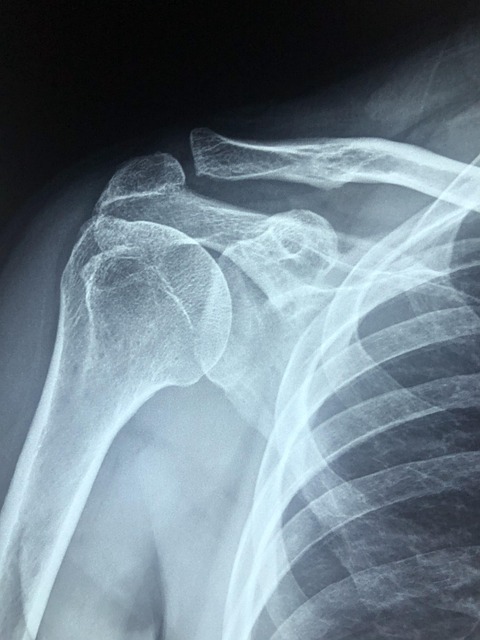

오십견·목 디스크 초기 증상

어깨 결림이 단순한 뻐근함을 넘어 팔을 들기 힘들거나, 한쪽 어깨만 지속적으로 아프다면 오십견 또는 경추 디스크 초기 신호일 수 있습니다.

이 경우 스트레칭만으로는 개선이 어렵습니다.병원진료가 필수입니다.